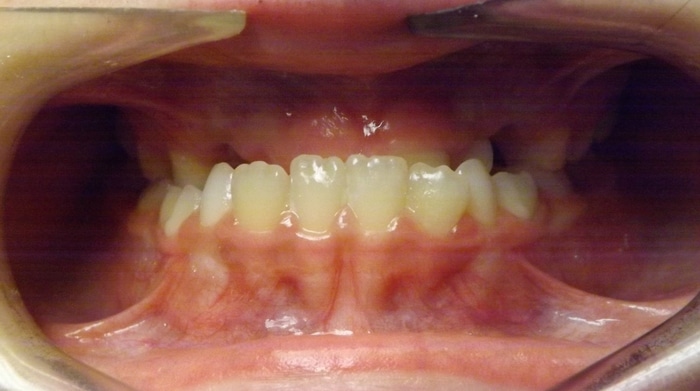

EMILY’S SMILE JOURNEY

Emily began with us as a Phase I patient and we just recently debanded her from Phase II. These progression photos show you that starting early allows us to not just straighten the teeth, but also change the patient’s jaw shape. Emily was a dedicated patient and did great with treatment. Her results speak volumes! We were able to correct her severe underbite and Class III skeletal imbalance without needing jaw surgery.